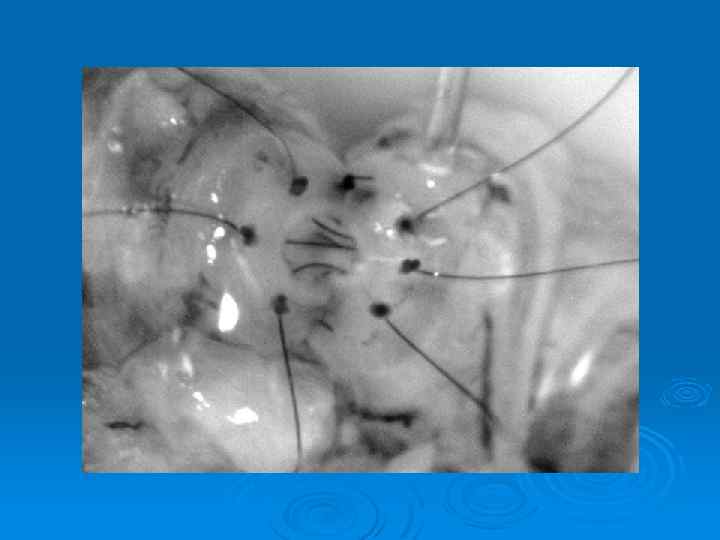

Перекрут яичка: лечение Ø Только хирургическое Ø Dead-Line 6 часов Ø Перекрут всегда к центру тела Ø Ревизия яичка, оценка выраженности перекрута и жизнеспособности органа Ø Фиксация обоих яичек к стенке мошонки

Перекрут левого яичка, некроз

До операции: перекрут 1100 градусов, 14 часов